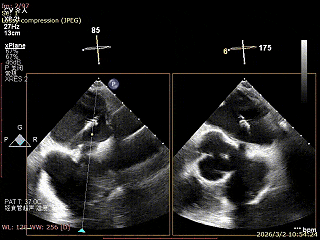

患者为房间隔缺损术后合并功能性二尖瓣反流(FMR),病变位于二尖瓣2区偏3区,因既往ASD修补史(可降解房间隔缺损封堵器),致房间隔穿刺区域存在瘢痕粘连、穿刺难度增加,于靠下靠后位置穿刺,避开房间隔缺损封堵伞,其余病变解剖结构相对简单;术前制定手术策略,拟使用1把XTR行二尖瓣修复,术中克服瘢痕粘连难点成功完成房间隔穿刺,穿刺点距二尖瓣瓣环平面3.1cm,将XTR‑CDS送入左心房,通过”A”旋钮旋转180度借高度,LVOT切面夹子严重Huge,使用”+”旋钮一键消除Huge,通过操控“M”旋钮将二尖瓣夹精准定位于2区正上方,完成弹道测试及Orientation调整后,于2区将夹子送入左心室,顺利捕捞并夹持瓣叶后缓慢闭合夹臂;TEE检查示二尖瓣反流充分降低至微量,二尖瓣双孔组织桥稳定,跨瓣压差2mmHg,肺静脉逆流明显改善,手术安全顺利结束。

XPLAN切面2区偏3区中重度反流

3D enface 切面

3D enface观察反流